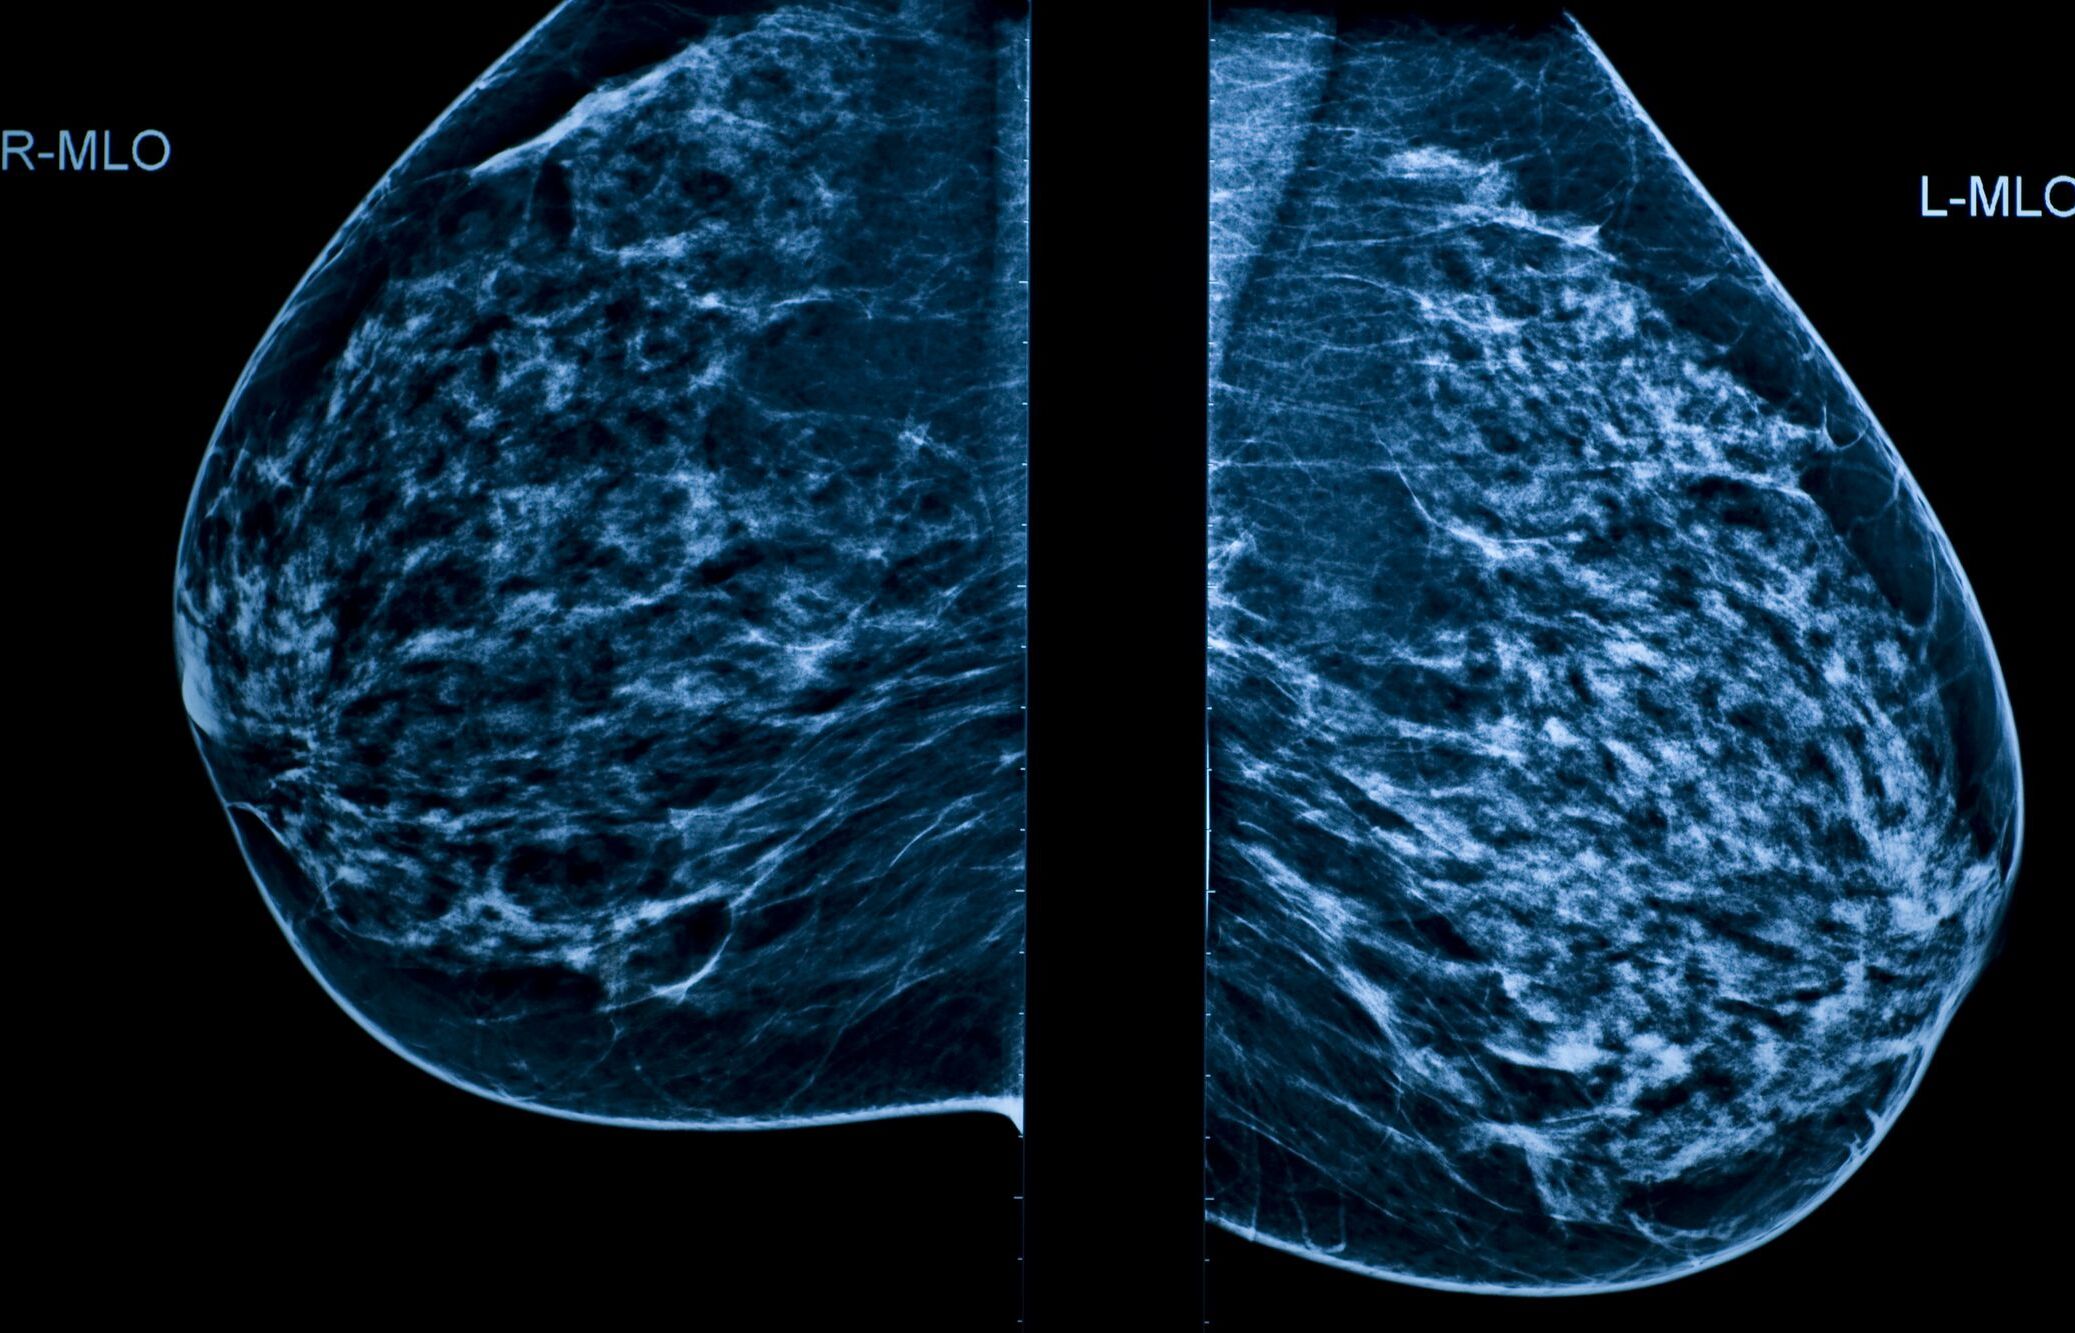

It's thought that metastatic disease is responsible for around 66% of the deaths related to breast cancer. How does breast cancer spread or recur?